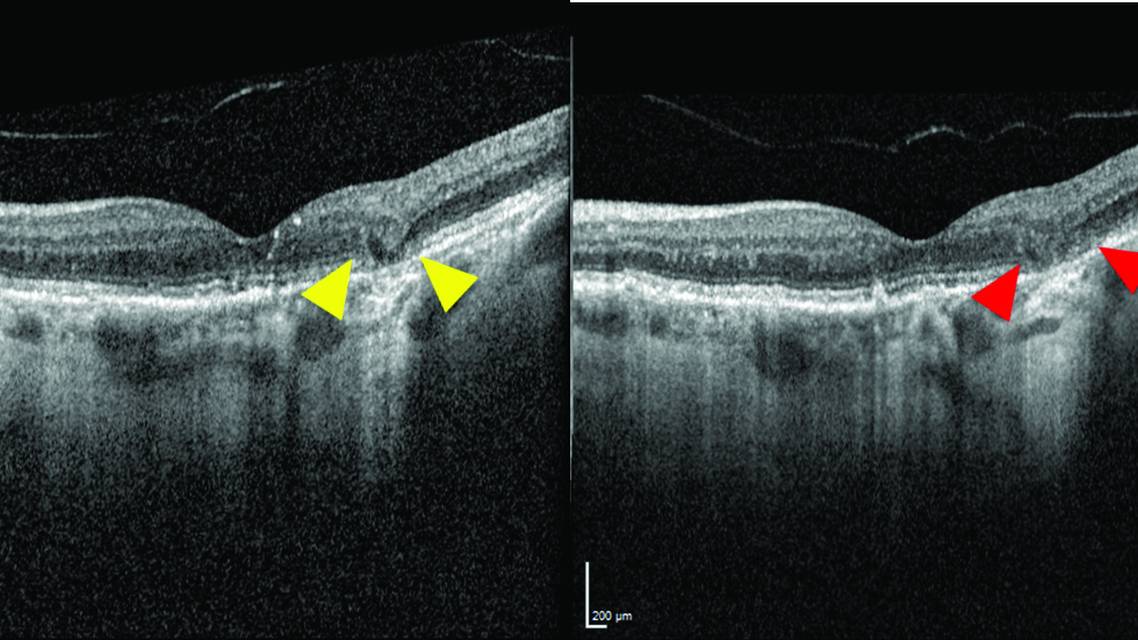

The Consensus on Atrophy Meeting (CAM) group used OCT to broadly define the umbrella term macular atrophy as a loss of the outer retina, loss of the RPE, and choroidal hypertransmission. Whereas macular atrophy is a nonspecific term and can apply to atrophic changes associated with any condition from dry AMD to inherited retinal disease, the term GA applies specifically to macular atrophy secondary to dry AMD. CAM further classified GA into two primary categories: complete RPE and outer retinal atrophy (cRORA) and incomplete RPE and outer retinal atrophy (iRORA). For lesions to qualify as cRORA, they must meet all criteria for macular atrophy on OCT with at least 250 µm of both RPE loss and choroidal hypertransmission (Figure 5). As the name implies, iRORA applies to macular atrophy that does not meet all three criteria to be classified as cRORA (Figure 6). Some early evidence suggests that iRORA may carry an increased risk of progression to cRORA and/or GA.3

An OCT biomarker called nascent GA was recently described and is currently the best-known risk factor for progression to cRORA and/or GA. Nascent GA is defined on OCT by the presence of subsidence—a sinking appearance of the outer plexiform layer and inner nuclear layer—and/or a hyporeflective wedge in the Henle fiber layer. Features of iRORA are often present in nascent GA, but they are not defining characteristics of nascent GA (Figure 7). The probability of lesion progression to GA within 24 months increased to 38% when nascent GA was present on OCT.4 The Table summarizes the differences in the CAM group’s OCT classification of macular atrophy and GA versus nascent GA.